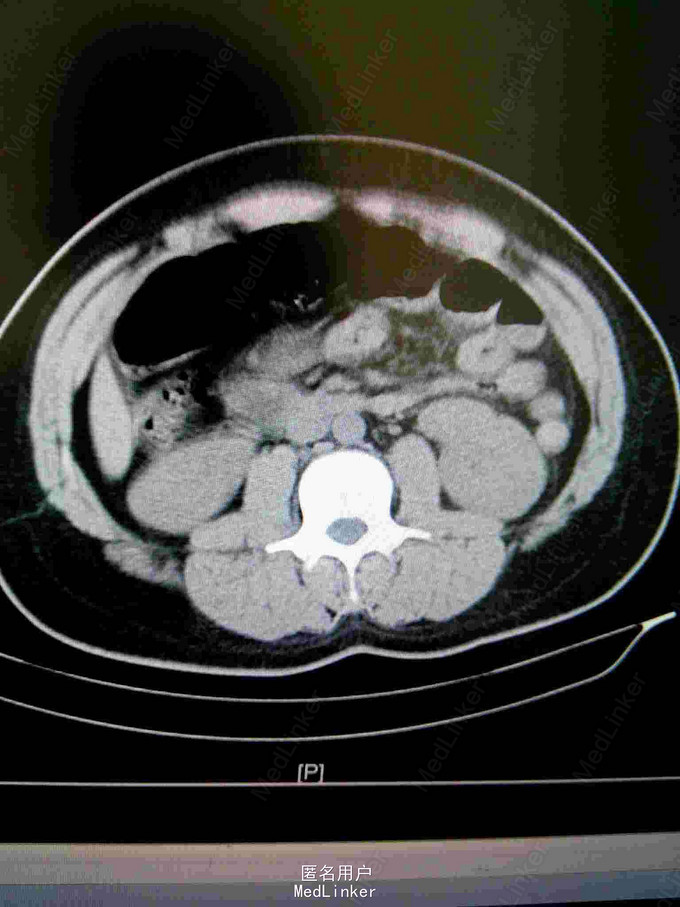

23岁男性患者,非洲加纳人,因"腹部疼痛半天"来院,现病史:患者半天前无明显诱因出现腹部疼痛,以下腹部持续性疼痛为主,阵发性加重,无发热,无呕吐,无腹胀腹泻,无尿频尿急尿痛等不适。患者有镰状细胞性贫血病史多年。

查体:神清,生命征平稳,急性痛苦面容,大汗淋淋,腹平,下腹部压痛明显,可疑反跳痛,无明显固定压痛点,上腹部轻度压痛,肝脾肋下未及,墨非氏征阴性,未及包块,双肾区无压痛扣击痛,输尿管行程无压痛,移动性 胞 浊音阴性,肠鸣音活跃。查血常规白细正常,中性正常,HGB95g/l,HCT26.7%,MC63.7fl,MCH22.7pg,MCHC356g/l,红细胞分布宽度差异23.7%,红细胞分布宽度标准53fl.淀粉酶正常。

镰状细胞性贫血并发肠绞痛。治疗:予补液,扩容,解痉止痛等对症处理。